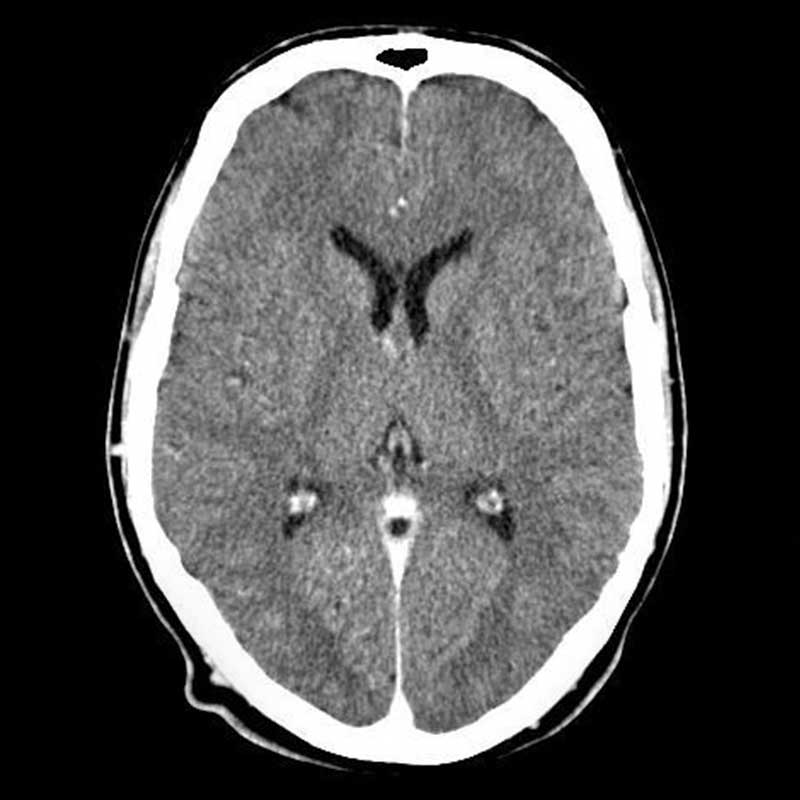

The Curious Case of Severe Traumatic Brain Injury

by Dr. John Leggins

The Curious Case of Severe Traumatic Brain Injury

by Dr. John Leggins